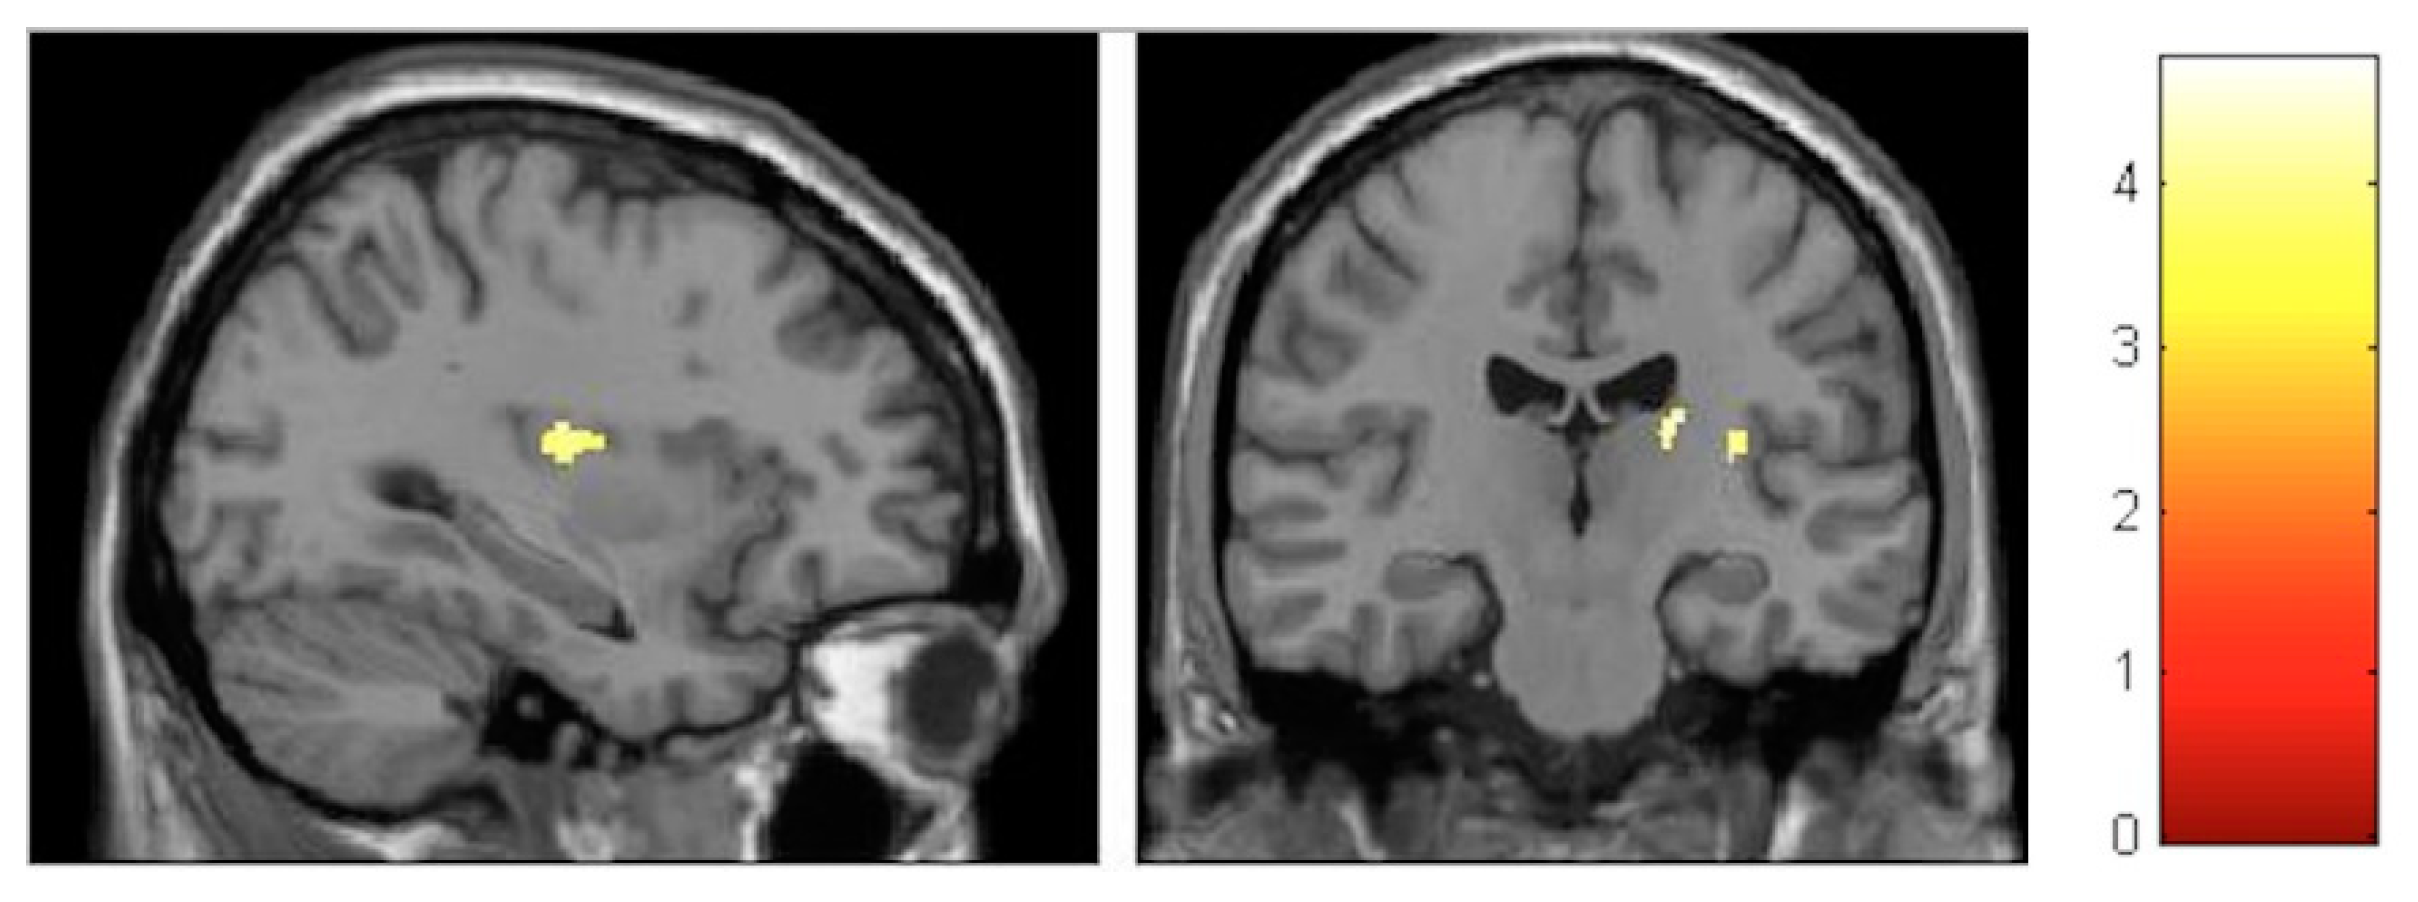

| Effect | Brain Region | Left Hemisphere MNI Coordinates (Cluster Size in Voxels) | T | d | Right Hemisphere MNI Coordinates (Cluster Size in Voxels) | T | d |

|---|---|---|---|---|---|---|---|

| Increment | Sensory-motor | −8, −32, 60 (314) | 5.17 | 0.39 | 11, −29, 60 (1087) | 6.09 | 0.41 |

| Decrement | Hippocampus | 27, −30, −6 (133) 23, −2, −17 (119) | 4.06 4.74 | 0.37 0.38 | |||

| Decrement | Insula | −33, −12, 18 (586) | 5.57 | 0.40 | 33, −17, 17 (797) | 6.17 | 0.41 |

| Decrement | Putamen | −26, 8, 6 (631) | 4.72 | 0.38 | 21, 11, 2 (134) | 4.22 | 0.38 |

| Decrement | Cerebellum | −11, −45, −23 (245) | 3.84 | 0.36 | 11, −65, −23 (224) | 3.99 | 0.37 |